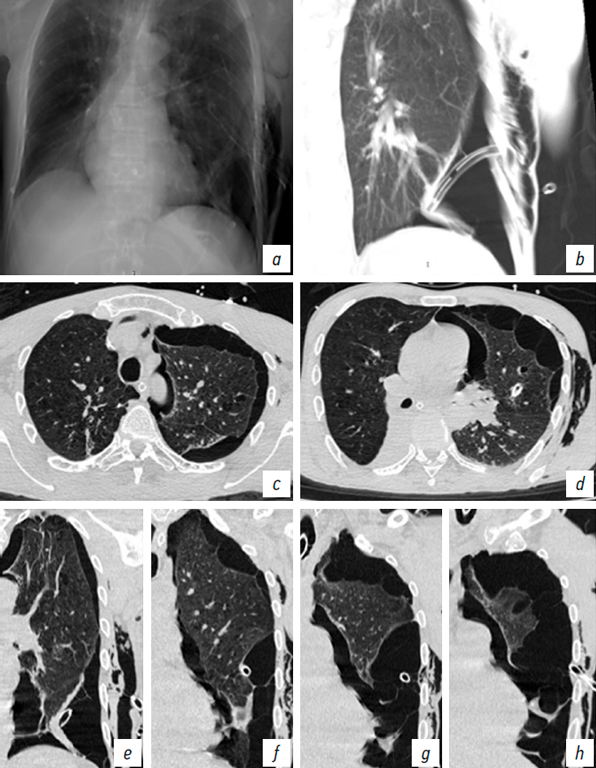

Furthermore, unilateral coexistence of pneumothorax and EPS emphysema was observed in five patients (Fig. 6). In three of these patients, the drainage tube was positioned in the EPS, which resulted in failure to drain the pleural cavity, progressive clinical deterioration, and the development of subcutaneous emphysema (Fig. 7). In one case, severe EPS emphysema was associated with respiratory failure (Fig. 8). US revealed findings characteristic of pneumothorax, including the absence of pleural sliding (Fig. 9).

Fig. 8. Patient U. a, chest X-ray, anteroposterior view; Chest CT: b, coronal reconstruction with 5-mm slice thickness in “Average” mode; c, d, axial plane; e–h, coronal plane through the left hemithorax. Massive extrapleural emphysema on the left side. Chest drain placed in the left extrapleural space compressing the lung. Subcutaneous emphysema left side.

Рис. 8. Пациент У. a — рентгенограмма органов груди в прямой проекции. КТ органов груди: b — реконструкция во фронтальной плоскости с толщиной среза 5 см в режиме «Average»; c, d — аксиальная плоскость; e–h — фронтальная плоскость левый гемиторакс. Массивная эмфизема ЭПП слева. Дренаж в ЭПП слева, компримирующий легкое. Подкожная эмфизема слева.